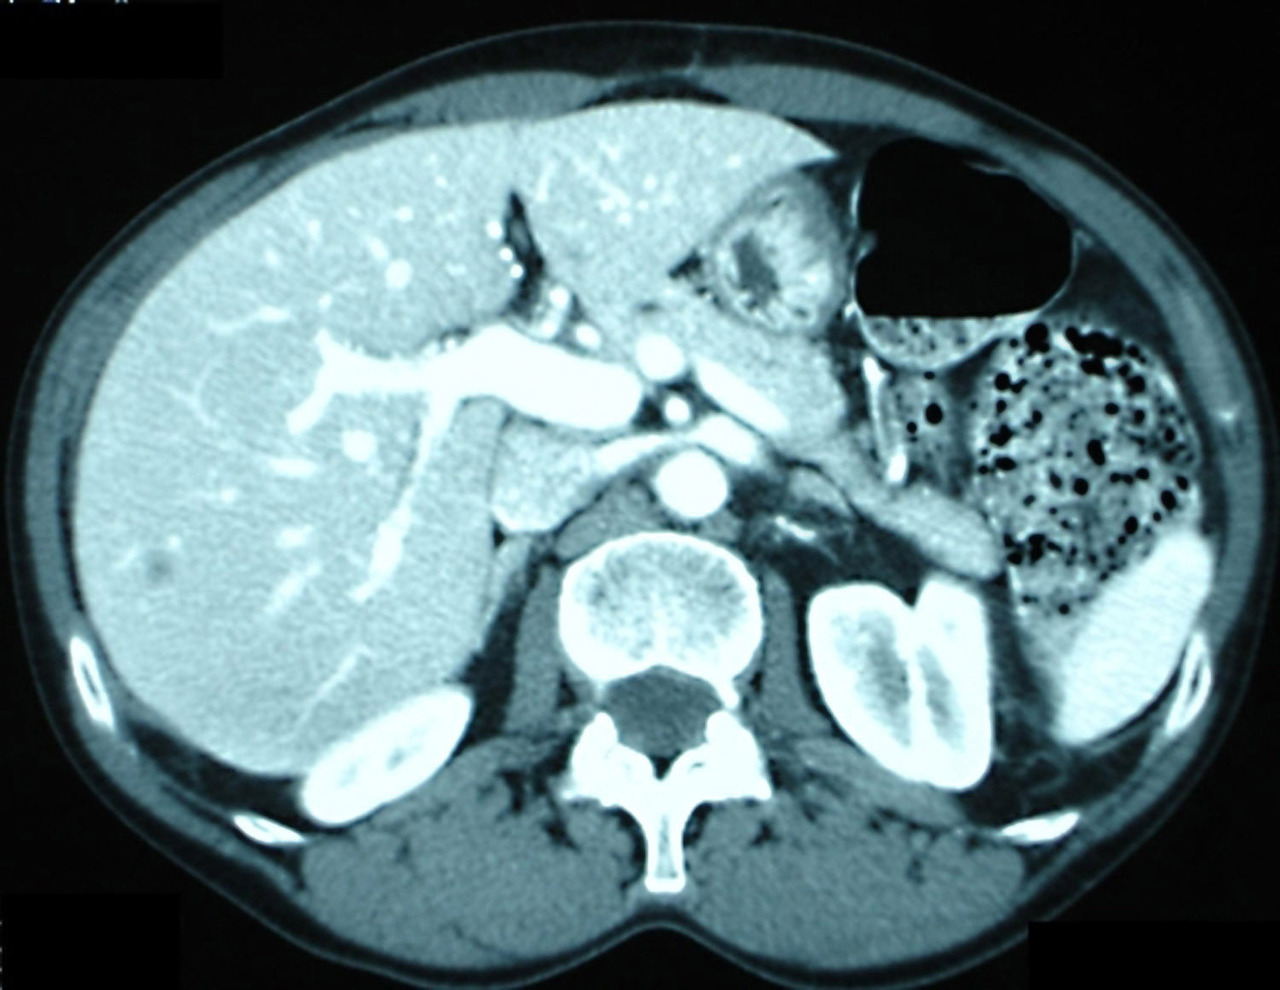

Quel est votre diagnostic ? Un foie normal Un abcès hépatique Une métastase hépatique Un kyste Une cholécystite OK Il s’agit d’une tomodensitométrie hépatique montrant une métastase hépatique unique d’un cancer du côlon. Dans 60 à 80 % des cas, les cancers du côlon ou du rectum se développent sur une lésion préexistante, le polype adénomateux. Valider mes réponses